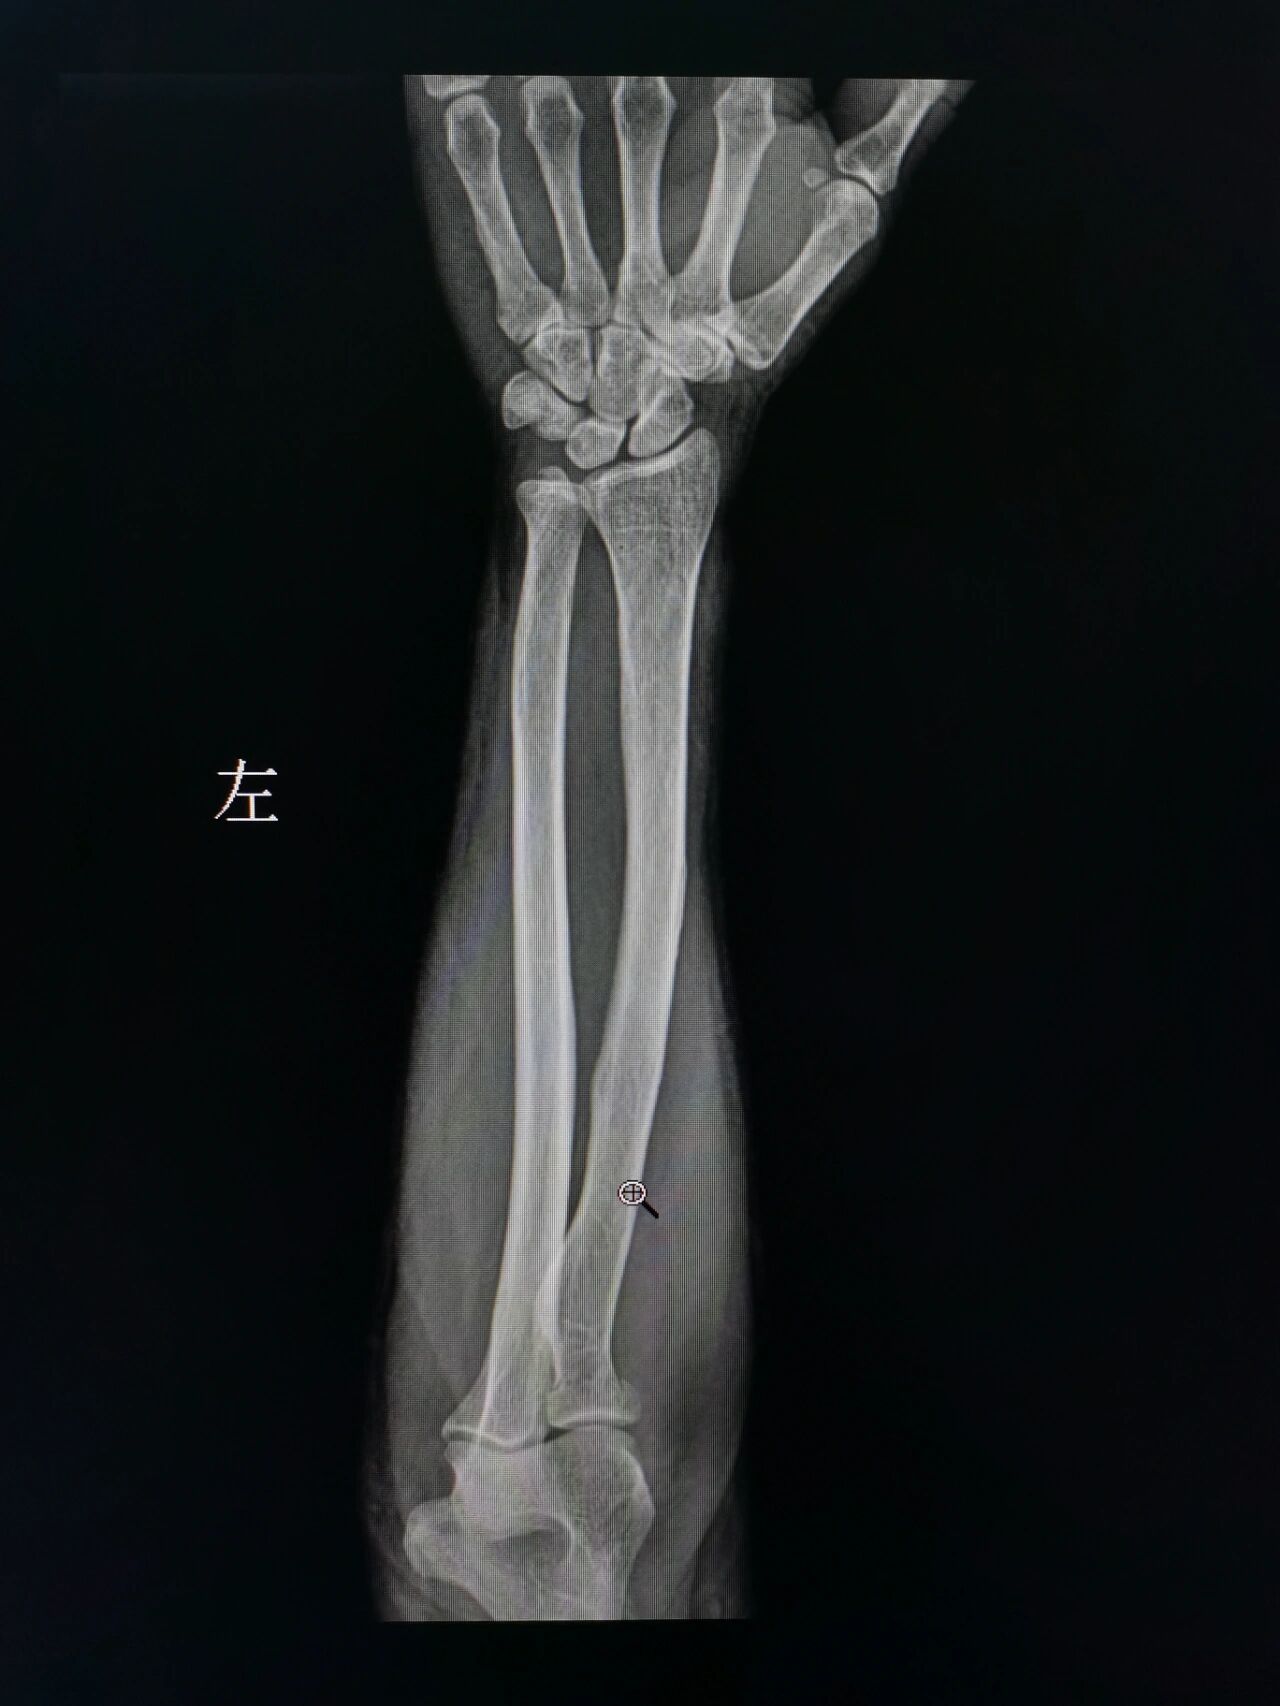

男孩12岁外伤至左尺桡骨下端骨折

左尺桡骨骨髓炎.